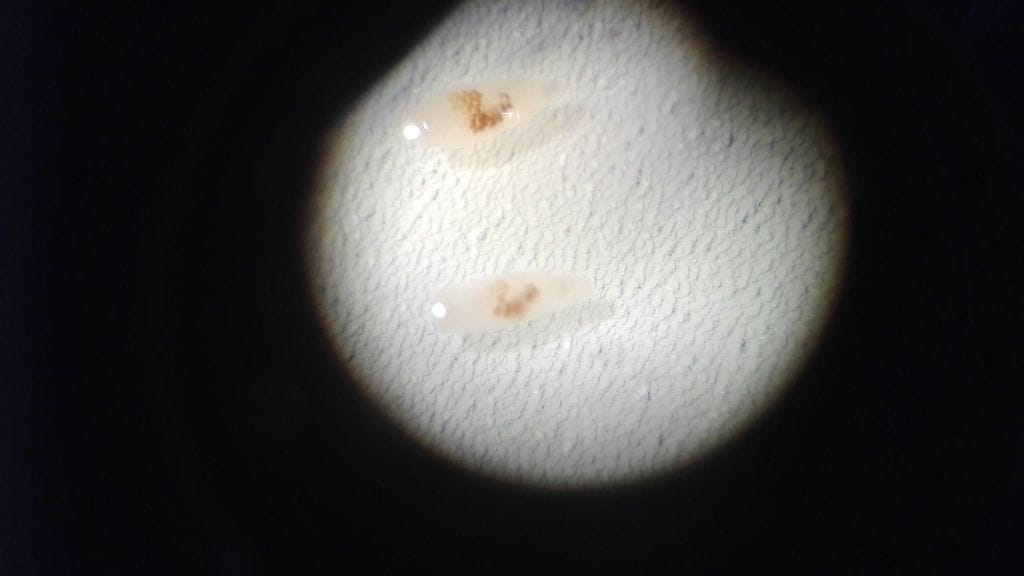

Suomenlahdesta pyydetyistä särjistä on löydetty imumatojen toukkamuotoja, kertoo elintarviketurvallisuusvirasto Evira.

Maksamadot voivat tarttua raakaa kalaa syöviin koiriin, kissoihin ja ihmisiin